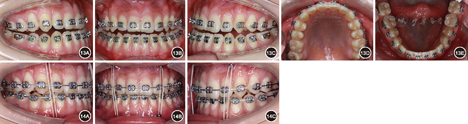

患者女性,21岁。主诉:"地包天",面部不美观,要求改善面型。否认家族史。

患者正面观基本对称,面下1/3略长。侧面凹面型,鼻旁区凹陷,下颌前突。口内检查:左右侧磨牙完全近中关系;前牙轻度开

1.5 mm,覆盖-4.0 mm;上牙列拥挤,下牙列舌向倾斜无拥挤。上中线右偏2.0 mm,下中线右偏2.5 mm。X线检查示上颌后缩下颌前突。头影测量显示SNA角77.56°,SNB角81.87°,ANB角-4.31°,Wits值17.93 mm,L1/MP角72.12°。

安氏Ⅲ类错

畸形,毛氏Ⅱ1+Ⅳ2;骨性Ⅲ类,上颌后缩下颌前突。

详细向患者阐述手术提前方案与传统术前正畸方案的优缺点及治疗风险后,患者选择手术提前方案并签署知情同意书。拼对模型后发现,该患者不存在明显的手术

干扰点,故直接行正颌手术纠正骨性不调。术前粘贴矫治器,置入0.356 mm(0.014英寸)镍钛圆丝作为正畸初始弓丝。转正颌外科行下颌双侧升支矢状劈开术。术中全麻下于上下颌前牙区及后牙区行种植体支抗植入术。术后2周去除颌间牵引,术后4周去除咬合板后行术后正畸。术后种植体支抗颌间牵引预防复发。术后正畸25个月,总疗程26个月。